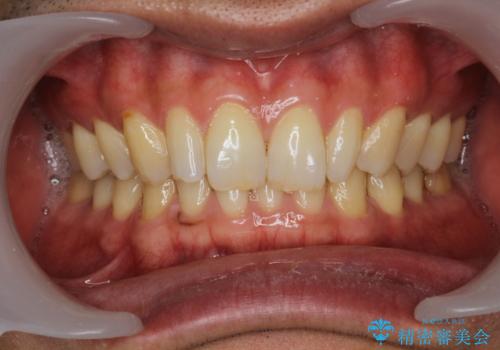

PMTC60分コースで取れるだけステイン落とし

担当医 歯科衛生士